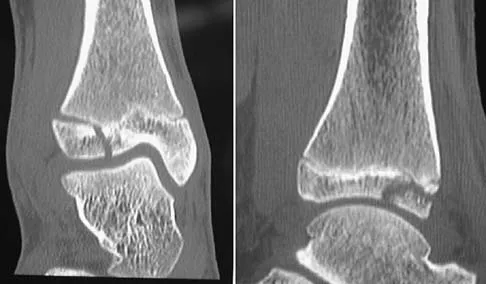

Figures 45a through 45c show the radiograph, CT scan, and MRI scan of a 15-year-old boy who has lateral ankle pain. What is the most likely diagnosis?

Options:

- Stress fracture of the calcaneus

- Rupture of the plantar fascia

- Early traumatic arthritis of the subtalar joint

- Calcaneonavicular fibrous coalition

- Disruption of the os peroneum

Correct Answer: Calcaneonavicular fibrous coalition

Explanation:

The elongated anterior process of the calcaneus reaching distally toward the navicular is an abnormal finding. Instead of viewing the rounded, blunt distal anterior process of the calcaneus, a bridge extends to the navicular, albeit incomplete. These findings are consistent with a fibrous coalition. CT can reveal a stress fracture of the calcaneus, arthritis of the subtalar joint with subchondral cysts, or an os peroneal bone disruption in the peroneus longus, but those entities are not shown here. The plantar fascia is intact. Richardson EG: Sesamoids and accessory bones of the foot, in Coughlin MJ, Mann RA (eds): Surgery of the Foot and Ankle, ed 7. St Louis, MO, Mosby, 1999, pp 702-732.